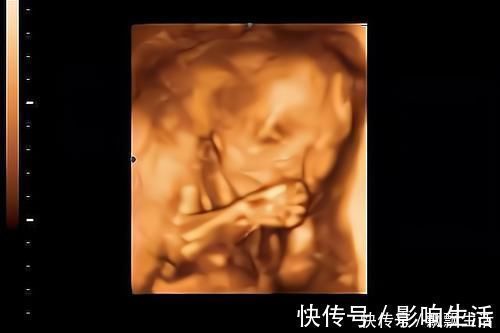

四维彩超,大多是排畸时做,看得会更清楚些,而且还会把当时拍到的胎儿样子,定格下来作为纪念。

检查时胎儿的“表现”,也可以作为出生后性格的参考,在肚子里就爱搞怪的宝宝,出生后也大多比较淘气。

四维彩超一次不能顺利通过也不用太担心,大多是正常,可能胎儿睡着了、遮挡住了,可以吃点甜食、起来活动下再做一次,也可以另约时间再做。